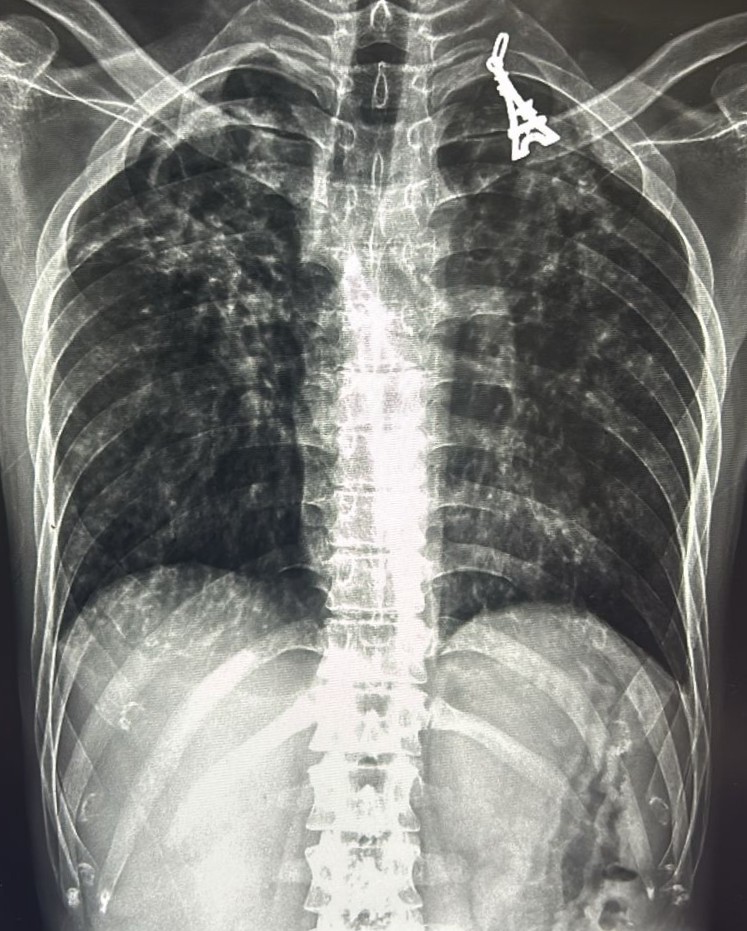

| 205 | IGGMC, Nagpur, Nagpur | P2 | 29-4267 | MOHAMMAD HANIF SUREYYA | Consent taken on Paper | 55 Yrs. |

Provisional Diag : PTB?

Final Diag : PNAEMOTHORAX /CLINICALLY DIAGNOSED PTB |

TB Case (Confirmed) | LEFT SIDED PNAEMOTHORAX | Abnormality visible on x-ray |

View |

|||